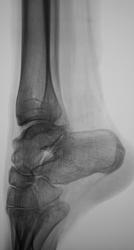

Пол пациента: Женский пол Тип патологии: Другое Область исследования: Скелетно-мышечная система Методы исследования: Rg Направлен с диагнозом деформации голеностопного сустава https://radiomed.ru/sites/default/files/styles/case_slider_image/public/user/12/2.dscn1417.jpg?itok=gXxfDKZ1 ID:27934 Чт, 11/04/2013 - 01:26 #1 Vikkur Не на сайте Был на сайте: 4 года 8 месяцев назад Зарегистрирован: 24.09.2009 - 14:34 Публикации: 1749 Уважаемый Валентин Львович была ли травма в анамнезе? больно таранная кость странная. Виктор. Чт, 11/04/2013 - 13:41 #2 Демчев Валентин... Не на сайте Был на сайте: 7 лет 7 месяцев назад Зарегистрирован: 08.02.2011 - 15:40 Публикации: 445 Смею предположить м.б. у пациента эквинусная деформация а отсюда и "странная" таранная кость. Чт, 11/04/2013 - 14:39 #3 Глазков Игорь А... Не на сайте Был на сайте: 9 месяцев 3 недели назад Зарегистрирован: 19.12.2008 - 20:41 Публикации: 1597 может быть последствием ДОА. Хотя травму тоже нельзя сбрасывать со счетов. Прийди к Себе Пт, 12/04/2013 - 01:41 #4 Катенёв Валенти... Не на сайте Был на сайте: 7 лет 3 недели назад Зарегистрирован: 22.03.2008 - 22:15 Публикации: 54876 Vikkur wrote: Уважаемый Валентин Львович была ли травма в анамнезе? больно таранная кость странная. Травмы не было Пт, 12/04/2013 - 01:42 #5 Катенёв Валенти... Не на сайте Был на сайте: 7 лет 3 недели назад Зарегистрирован: 22.03.2008 - 22:15 Публикации: 54876 Чавой-то наши уважаемые ортопеды-травматологи эту ветку, ну совсем манкируют Пт, 12/04/2013 - 18:03 #6 Катенёв Валенти... Не на сайте Был на сайте: 7 лет 3 недели назад Зарегистрирован: 22.03.2008 - 22:15 Публикации: 54876 Vikkur wrote: больно таранная кость странная. Да, Вы правы уважаемый коллега, странноватая однако таранная кость, да и голеностоп, особенно на боковой, как из потустороннего мира... Пт, 12/04/2013 - 18:08 #7 Катенёв Валенти... Не на сайте Был на сайте: 7 лет 3 недели назад Зарегистрирован: 22.03.2008 - 22:15 Публикации: 54876 Демчев Валентин Анатольевич wrote: Смею предположить м.б. у пациента эквинусная деформация а отсюда и "странная" таранная кость. Это вы на "конскую стопу" намекаете? Пт, 12/04/2013 - 18:09 #8 Катенёв Валенти... Не на сайте Был на сайте: 7 лет 3 недели назад Зарегистрирован: 22.03.2008 - 22:15 Публикации: 54876 Интересная однако линейная "тенюха"...Приложения: Пт, 12/04/2013 - 20:28 #9 Гриша Хата Не на сайте Был на сайте: 10 лет 2 недели назад Зарегистрирован: 09.02.2011 - 20:40 Публикации: 665 Это подошвенный апоневроз. Пт, 12/04/2013 - 21:22 #10 Катенёв Валенти... Не на сайте Был на сайте: 7 лет 3 недели назад Зарегистрирован: 22.03.2008 - 22:15 Публикации: 54876 Гриша Хата wrote: Это подошвенный апоневроз. +1. Остается вопрос - почему виден? Вс, 14/04/2013 - 10:21 #11 Варда Не на сайте Был на сайте: 4 года 11 месяцев назад Зарегистрирован: 01.10.2012 - 21:32 Публикации: 12 Боюсь предположить,что это плантарный фасцит,скорее его начальные проявления

Смею предположить м.б. у пациента эквинусная деформация а отсюда и "странная" таранная кость.

может быть последствием ДОА. Хотя травму тоже нельзя сбрасывать со счетов.

Травмы не было

Да, Вы правы уважаемый коллега, странноватая однако таранная кость, да и голеностоп, особенно на боковой, как из потустороннего мира...

Интересная однако линейная "тенюха"...

Это подошвенный апоневроз.

Остается вопрос - почему виден?

Боюсь предположить,что это плантарный фасцит,скорее его начальные проявления